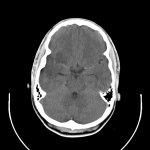

Meine CT

Aufnahmen: |

R(C)T = Röntgenstrahl Computer Tomographie

(ab 1972)

Das Gehirn wird mit Röntgenstrahlen

beschickt, die durch die unterschiedliche Dichte des Gewebes auf der

anderen Seite leicht gedämpft austreten. Dabei absorbiert dichteres

Gewebe die Strahlen stärker. Detektoren sammeln die austretenden

Strahlen, aus deren Intensität per Computer ein Bild dieser Scheibe

berechnet wird.

Problem: Röntgenstrahlung ist sehr energiereiche Strahlung und

kann Schäden verursachen.